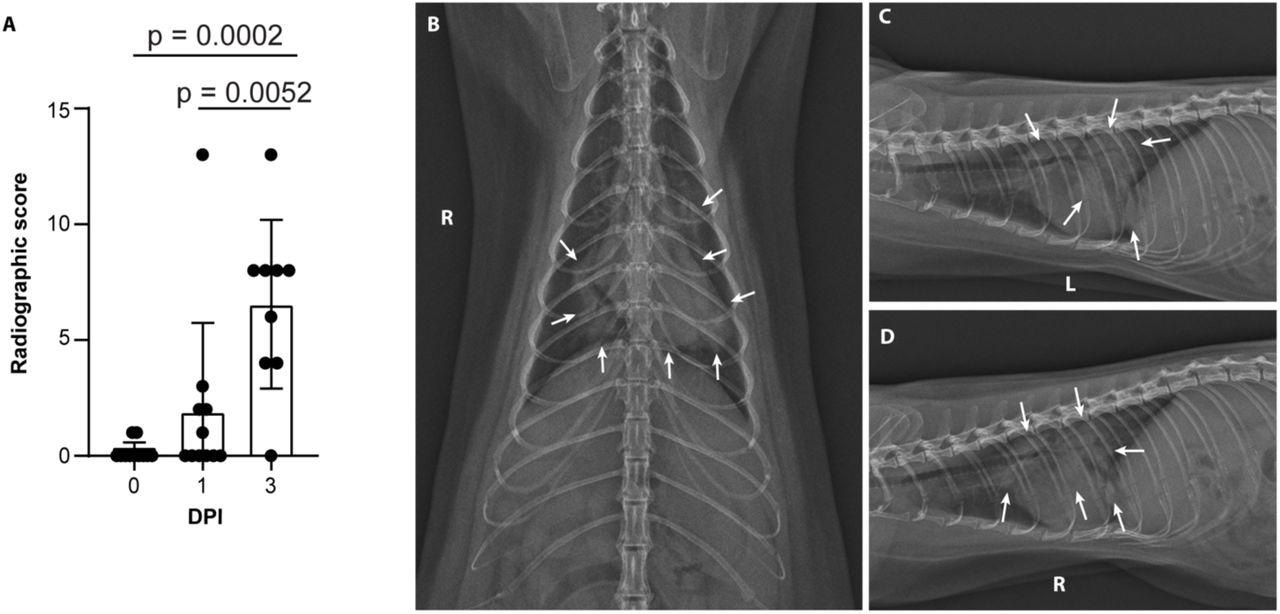

Minks develop severe COVID-19 infection 2 days after exposureSevere radiological changes after infection with SARS-CoV-2. (A) Compiled radiographic scores. Bar graph depicts the mean with standard deviation and individuals, ordinary one-way ANOVA with Tukey’s multiple comparisons test. Radiographs demonstrate multifocal pulmonary infiltrates, most severe in the left and right caudal lung lobes depicted in the (B) dorsoventral radiograph (C) left lateral and (D) right lateral radiograph on the evening of 2 days post-inoculation (DPI). Arrows depict grade 4 pulmonary disease in the left and right caudal lung lobes with grade 3 pulmonary disease in the right middle lung lobe and cranial subsegment of the left cranial lung lobe.

Severe radiological changes after infection with SARS-CoV-2. (A) Compiled radiographic scores. Bar graph depicts the mean with standard deviation and individuals, ordinary one-way ANOVA with Tukey’s multiple comparisons test. Radiographs demonstrate multifocal pulmonary infiltrates, most severe in the left and right caudal lung lobes depicted in the (B) dorsoventral radiograph (C) left lateral and (D) right lateral radiograph on the evening of 2 days post-inoculation (DPI). Arrows depict grade 4 pulmonary disease in the left and right caudal lung lobes with grade 3 pulmonary disease in the right middle lung lobe and cranial subsegment of the left cranial lung lobe.

Minks developed progressive pulmonary infiltrates consistent with viral pneumonia from ARDS on the first and third day after exposure.